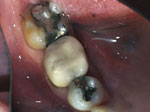

Onlays

Before  After

What's an Onlay?

It's a dentist-fabricated replacement of one or more cusps of your tooth. Dr. Mirmiran provides this valuable service because she feels that they are much more conservative than a full crown.

Porcelain Onlays are beautiful, feel as natural as your own tooth, and last 15-20 years.